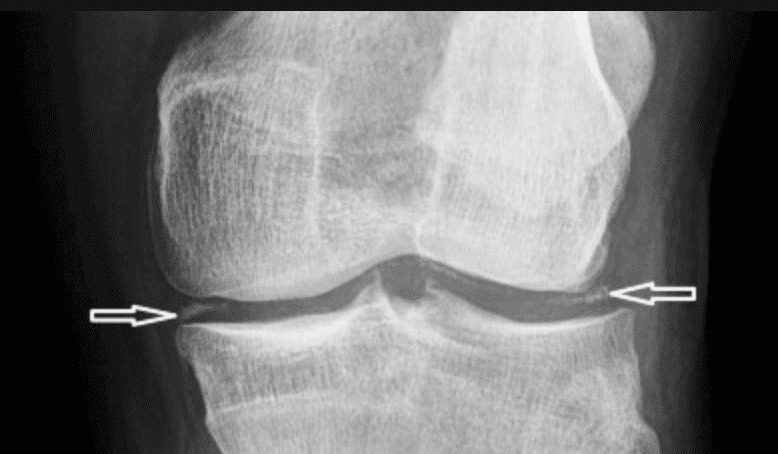

Phim chụp X-quang khớp bị ảnh hưởng có thể tiết lộ tổn thương khớp và các tinh thể lắng đọng trong sụn khớp.